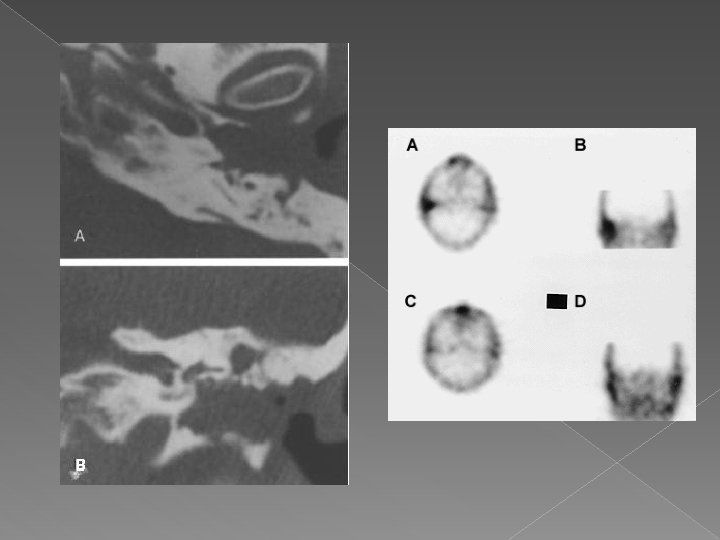

DIAGNOSIS • Diabetes • Advanced age • Severe otalgia • Granulation tissue • Cranial nerve involvement • Radiology